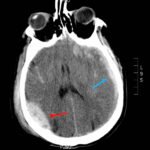

An epidural hematoma (EDH) is a potentially life-threatening intracranial hemorrhage (ICH) that may require emergency neurosurgical intervention to prevent rapid clinical decline. This case report discusses the presentation, diagnosis and neurosurgical intervention of an adult male who presented unresponsive and was found to have a right-sided epidural hematoma along with a left-sided subdural hematoma requiring surgical placement of an extra-ventricular drain. Although most epidural hematomas are easily visible on non-contrast computed tomography (CT), it is important to be able to recognize key diagnostic findings that separate epidural hematomas from other types of intracranial hemorrhages. While many are managed without surgery, it is important to know the presentation, progression, and diagnostic criteria that may warrant neurosurgical intervention to combat the effects of an expanding hematoma and increasing intracranial pressure.